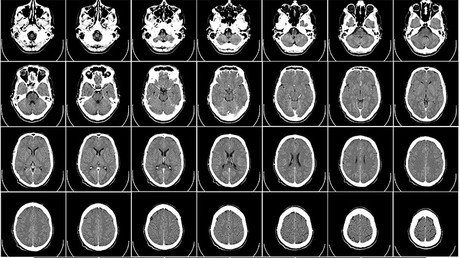

Durante décadas, el pueblo chamorro (indígenas de las Marianas) ha sido golpeado por una inquietante enfermedad cerebral progresiva bautizada por ellos como 'lytico-bodig'. Los primeros síntomas aparecen cuando las víctimas tienen entre 40 y 50 años, y cuando llegan a los 60 años empiezan a sufrir el tipo de agitación y la falta de coordinación que se aprecia en el párkinson. A continuación, aparecen los problemas de memoria característicos de esta enfermedad neurodegenerativa.

En el marco de una dieta experimental, los científicos administraron a monos nativos de África durante 140 días la misma dosis de BMAA que la que un habitante de la isla de Guam puede ingerir durante toda su vida. Como resultado, los animales desarrollaron signos típicos de la enfermedad neurodegenerativa: placas entre las neuronas con ovillos neurofibrilares en su interior.